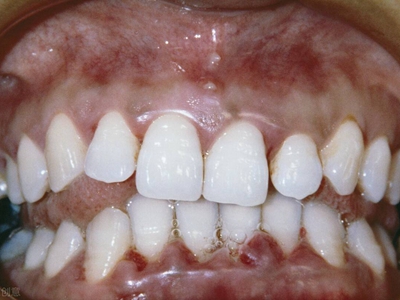

牙龈退缩上排多颗牙的牙根暴露图

牙龈退缩导致上排多颗牙齿的牙龈回缩,部分牙根暴露在外,伴有牙齿松动、口臭等症状,是由于牙周炎、局部受力过大等因素导致。